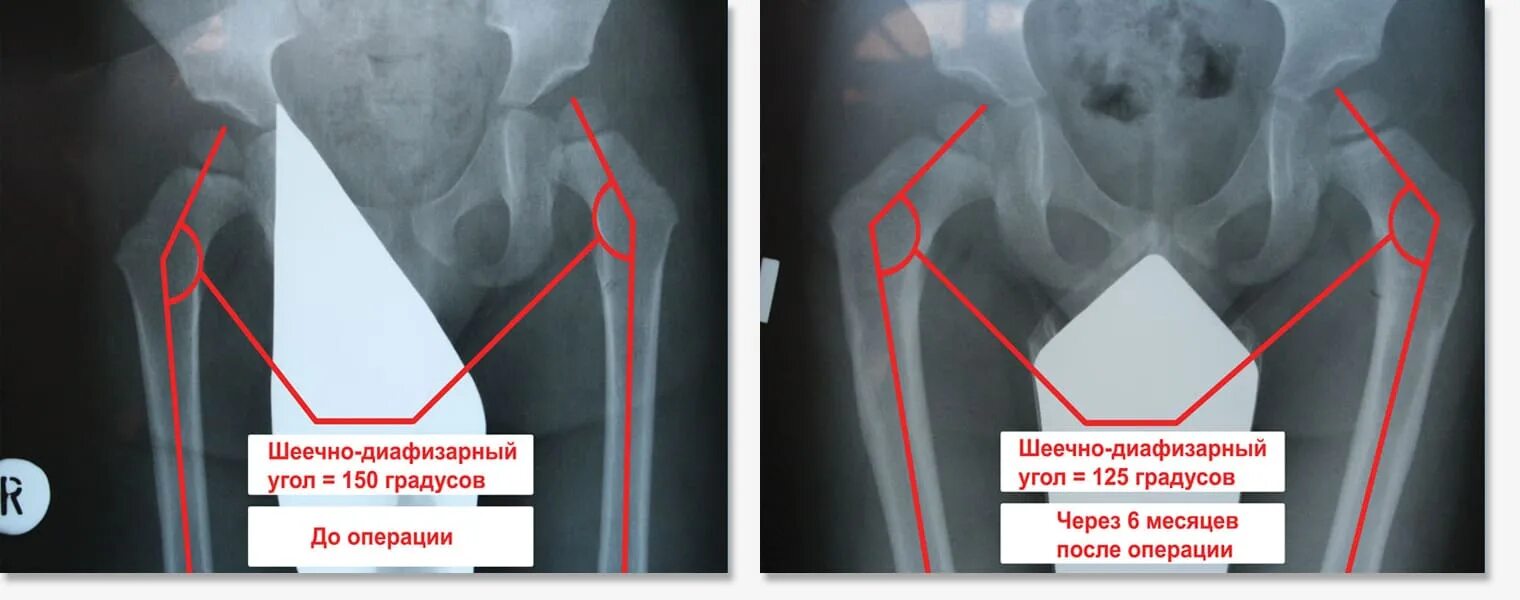

Электрофорез при дисплазии